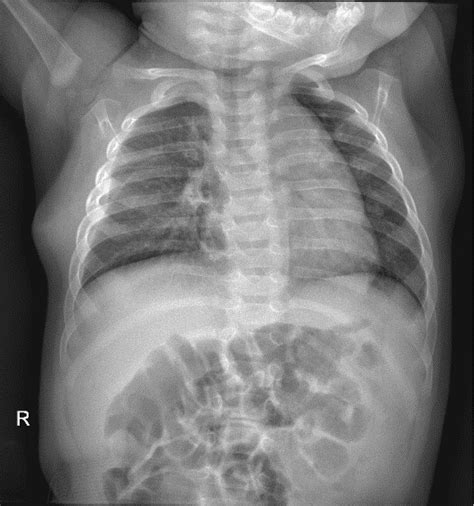

• Chest X-ray: This is the primary diagnostic tool for pneumothorax. A chest X-ray can show the presence of air in the pleural space and the extent of the lung collapse.